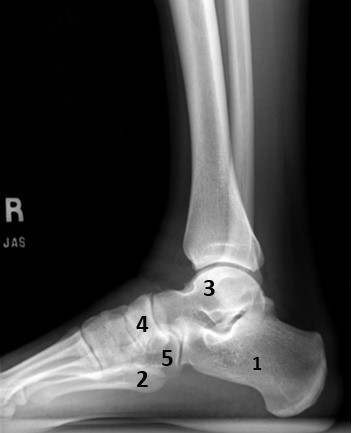

Which of the numbered tarsal bones is the cuboid?

A - 1

B - 4

C - 2

D - 5

E - 3

A

The Correct Answer is: D

The cuboid (5) is located proximal to the base of the fifth metatarsal (2) and articulates with the calcaneus (1) (A, C, and D). The talus is located directly above the calcaneus (3) and distal to the tibia (E). The navicular (